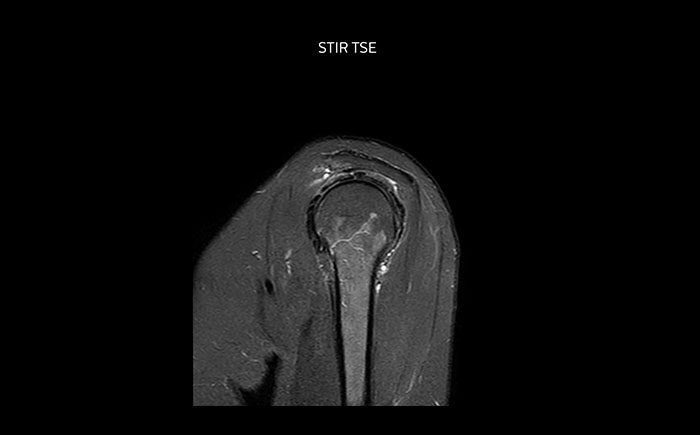

Shoulder MRI with high quality, large coverage

The Prodiva shoulder coil is very flexible and has large coverage, which makes good positioning easier, and that contributes to the superb image quality and high SNR that we get in our shoulder exams.

Scan time 2:55 min, FOV 160 mm,

acq voxels 0.55 x 0.83 x 3.0 mm.

Scan time 4:19 min, FOV 160 mm,

acq voxels 0.55 x 0.80 x 3.0 mm.

Scan time 2:50 min, FOV 160 mm,

acq voxels 0.70 x 0.99 x 3.0 mm.

Shoulder MRI with high quality, T2 SPIR

Shoulder MRI with high quality, mFFE

Shoulder MRI with high quality, STIR TSE